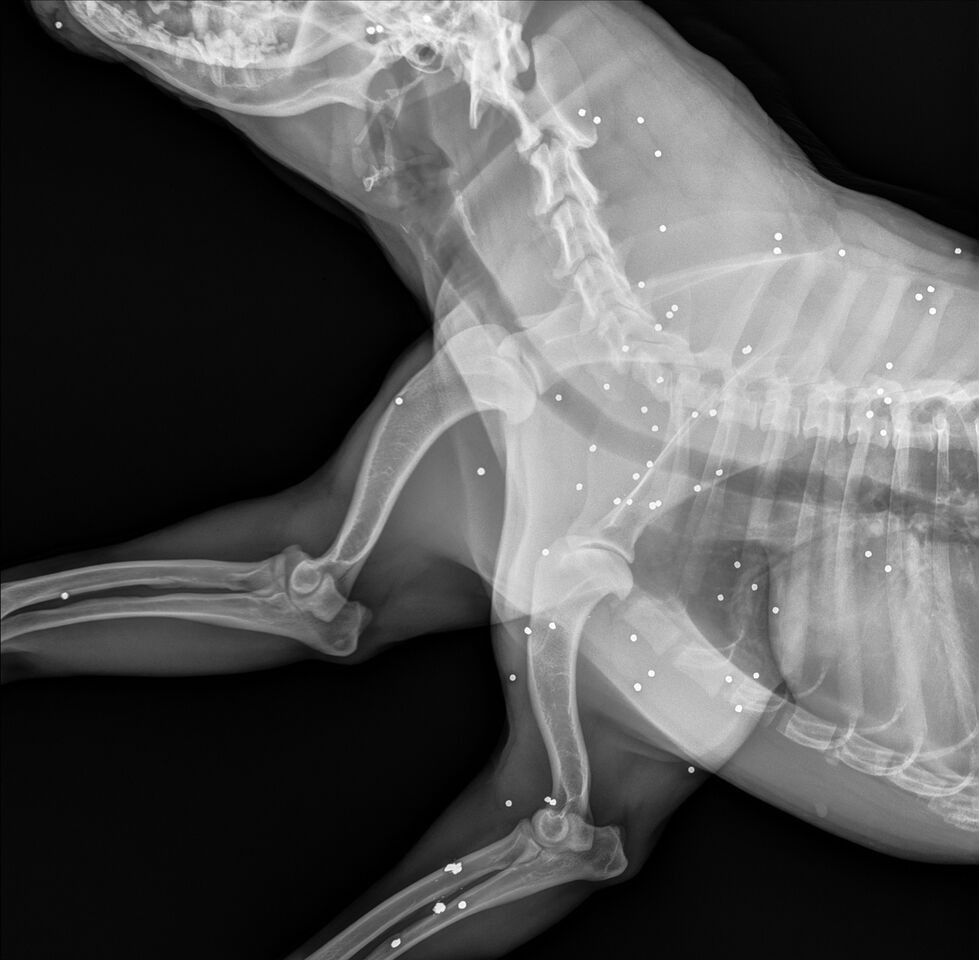

Nous lui avons fait passer une radio et nous avons découvert que Mama était criblé de petites balles de fusil de chasse, ce qui explique probablement pourquoi elle était si craintive à l'extérieur. Quelqu'un a dû lui tirer dessus par le passé.

Ces petites munitions généralement utilisées pour chasser les oiseaux ; leur présence en grand nombre dans le système de Mama reste donc inexpliquée.

À l'heure actuelle, les balles ne représentent pas de menace pour la santé de la chienne ; il n'est donc pas nécessaire de les enlever.Cependant, cela explique le comportement anxieux de Mama, qui est particulièrement appeurée lorsqu'elle est dehors. Cindy Szczudlo affirme: